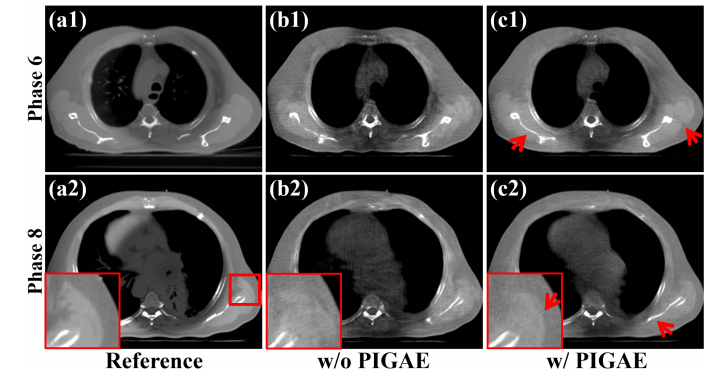

Fig. 10. Reconstructed results from Phases 6 and 8 on the simulated dataset.(a1)-(a2) Reference images reconstructed from full-sampled projections, (b1)-(b2) Images processed by RestoreNet without PIGAE module, (c1)-(c2) Images processed by RestoreNet with PIGAE module. The display window is [0.004, 0.014] mm-1 .

图10. 在模拟数据集中,相位6和8的重建结果。(a1)-(a2) 从全采样投影重建的参考图像,(b1)-(b2) 由不带PIGAE模块的RestoreNet处理的图像,(c1)-(c2) 由带PIGAE模块的RestoreNet处理的图像。显示窗口为 [0.004, 0.014] mm^-1。